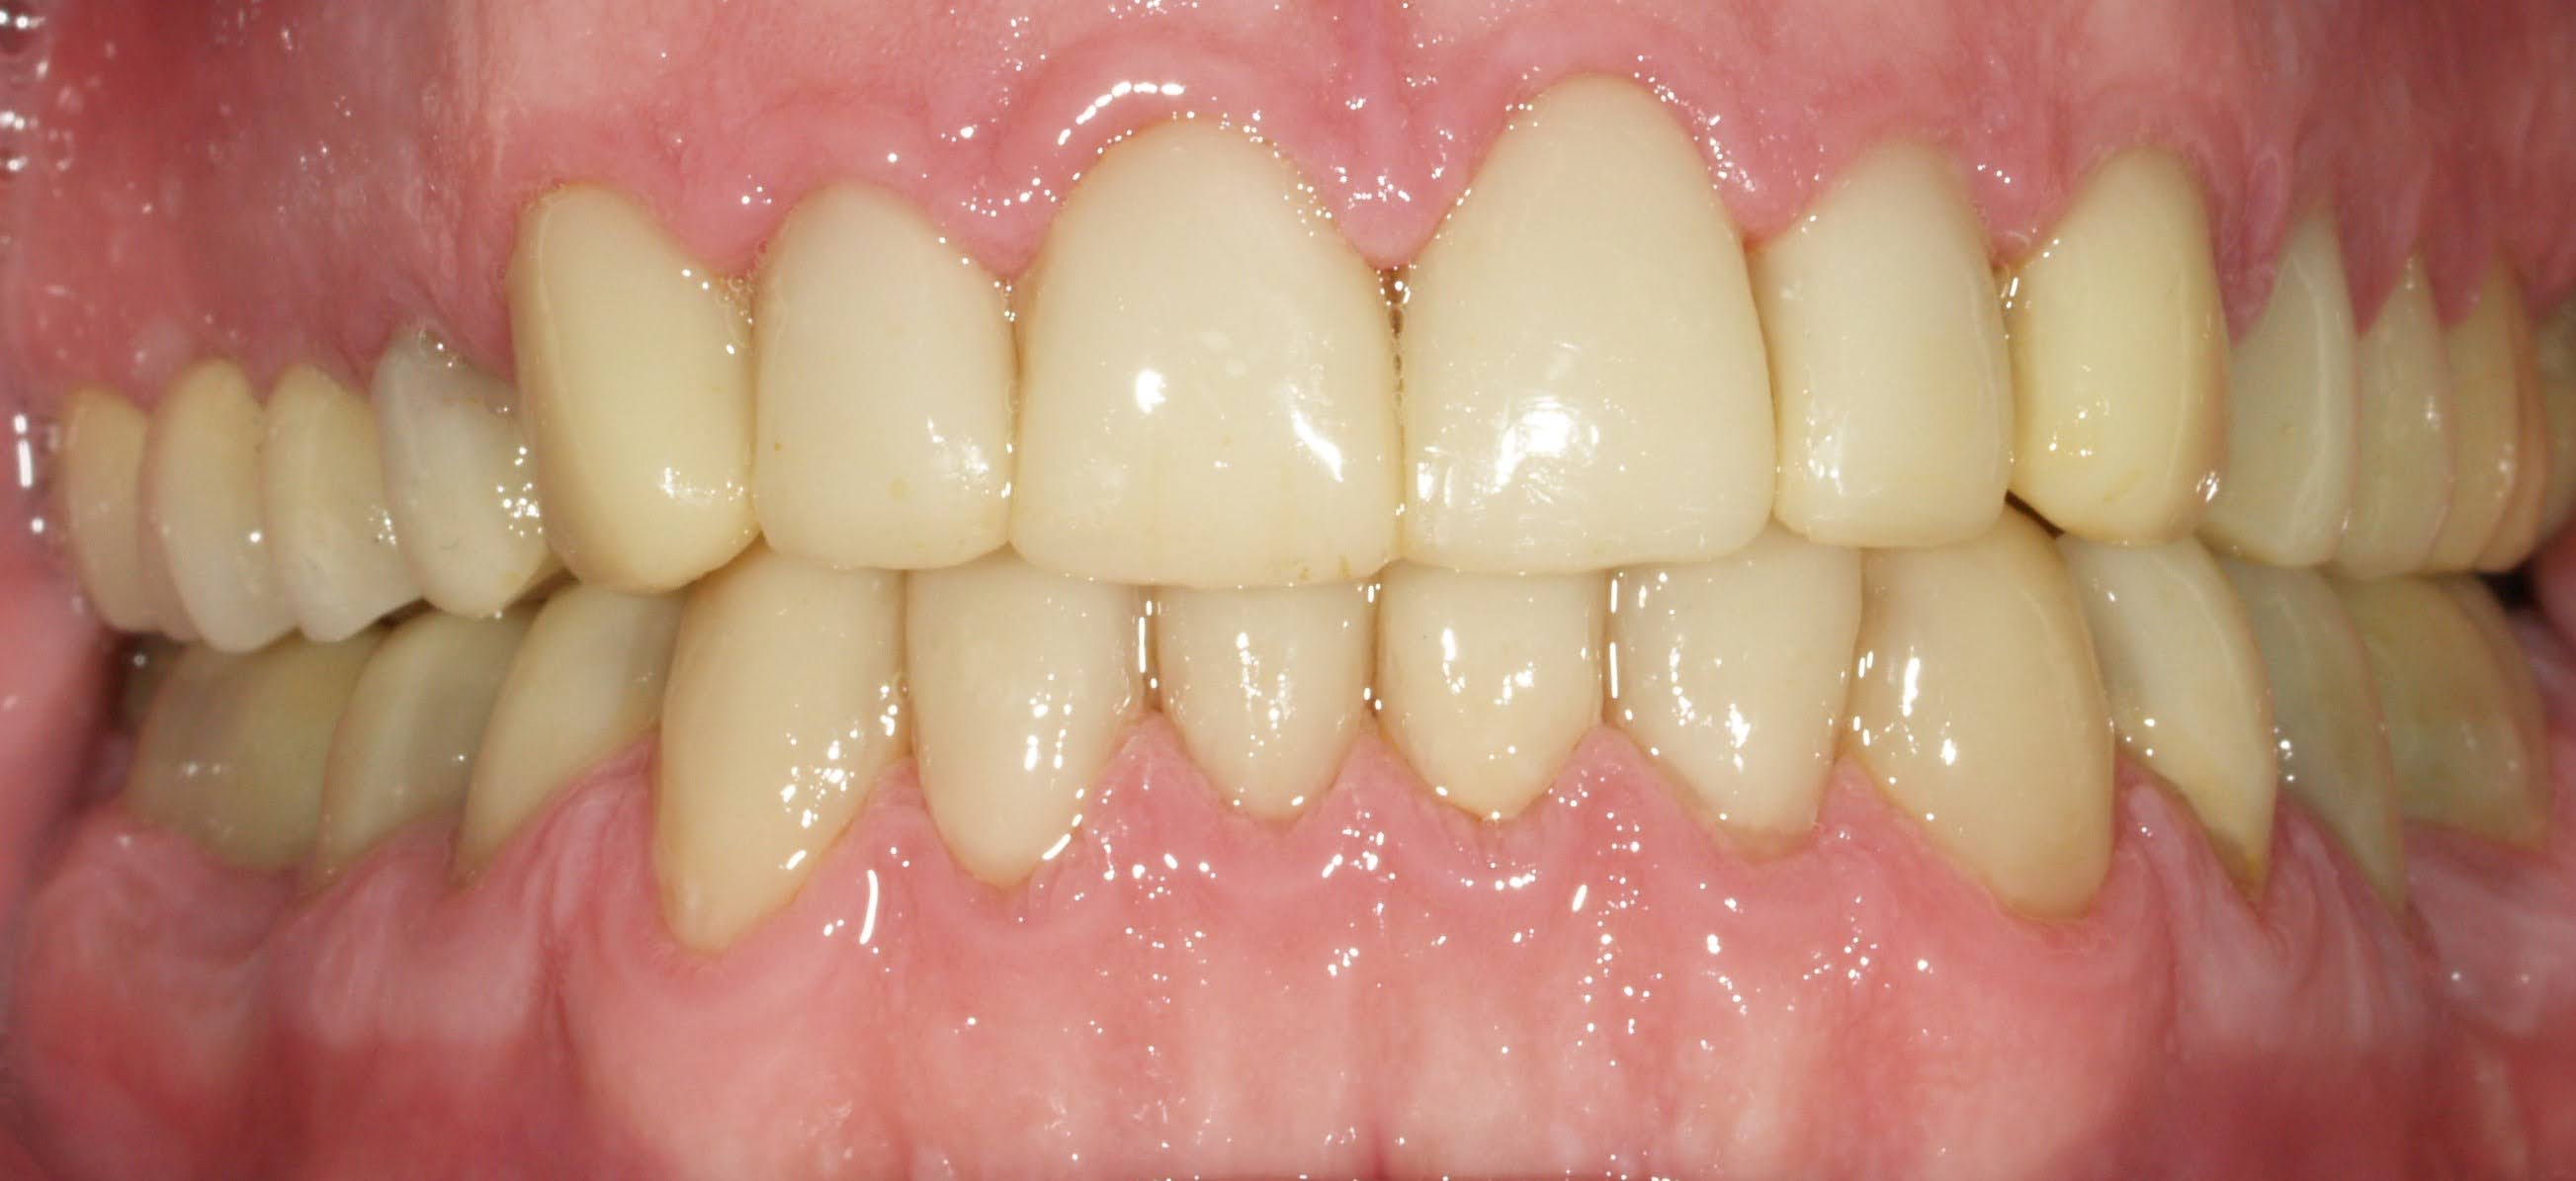

Carillas de porcelana

Carillas de porcelana - Antes Carillas de porcelana - Después

ANTES

DESPUÉS